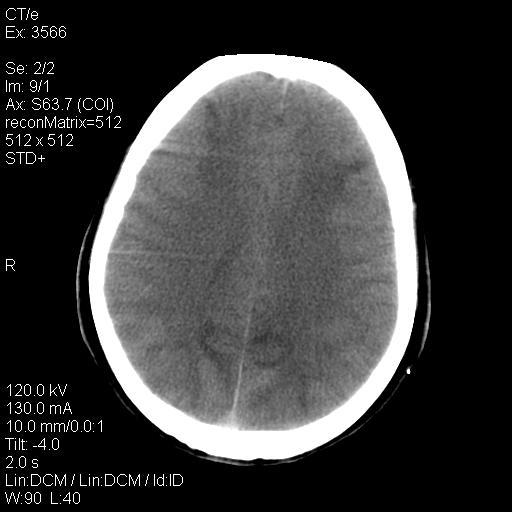

标题: CT9947:女,20岁,妊娠9个月,突然癫痫症状 [打印本页]

标题: CT9947:女,20岁,妊娠9个月,突然癫痫症状

双侧脑白质缺血缺氧性改变,并高度可疑“蛛网膜下腔出血”。

后可复性脑病,

考虑 妊娠子痫或妊高征

双侧脑白质缺血缺氧性改变.

考虑先兆子痫\\子痫致he,建议mri除外有无合并静脉窦血栓形成.

考虑pres

的确应该考虑可逆性后部脑病综合症--pres。感谢天南地北老师的指引,又学了一招儿,开心,呵呵!

考虑可逆性后部脑病综合症

支持pres